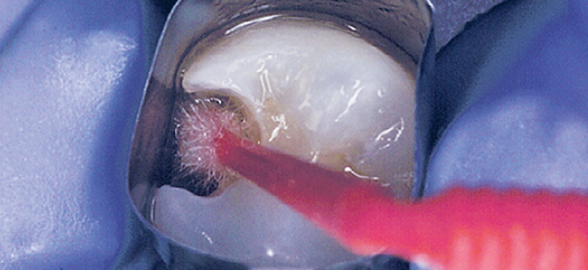

Los retratamientos de conductos radiculares o re-endodoncia del diente, son inevitables aun con pautas clínicas ideales.